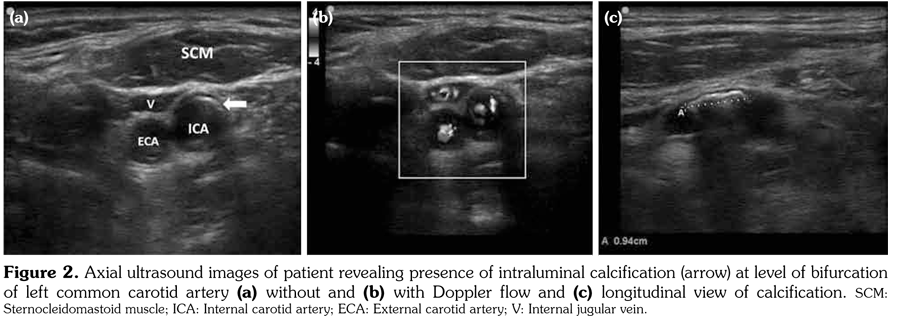

An 80-year-old female patient was examined due to complaint of neck pain over the last year which has aggravated recently. She denied history of trauma. Her medical history indicated that she was taking some medications for hypertension and coronary artery disease. Physical examination was compatible with cervical osteoarthritis with limited cervical range of motion in all directions and tenderness to palpation. Laboratory findings including complete blood count, erythrocyte sedimentation rate, C-reactive protein, serum calcium, phosphorus, parathyroid hormone, and vitamin D levels were within normal ranges. On radiological evaluation, cervical X-ray revealed a calcified mass in the left mid-paravertebral region with cervical degenerative changes (Figure 1). At first glance, a calcification inside the cervical muscles was suspected. Ultrasonographic examination of the cervical region revealed the presence of intraluminal calcification at the level of the bifurcation of the left common carotid artery (Figure 2a-c). The patient was referred to neurology department for being at risk for stroke.

Carotid arteries are the major vascular structures that deliver blood to brain. A blockage in carotid arteries can lead to stroke which is typically caused by atherosclerosis.(1) The artery-wall thickens as a result of invasion and deposit of white blood cells and proliferation of intimalsmooth-muscle cell creating a fatty plaque which is known as atherosclerosis.(2) These deposits also contain cellular waste, cholesterol, and triglycerides with often occurring calcification.(2) Therefore, paravertebral calcifications seen on X-ray might be inside the vessels, particularly in the elderly. Complications of the carotid artery calcification should be kept in mind, so that the patient can be referred to the relevant departments before occurrence of catastrophic consequences such as stroke. Ultrasonography should be the method of choice in confirming the diagnosis.(3)

Lastly, ultrasound gives not only an opportunity to evaluate musculoskeletal pathologies, but also offers visualization of a wide range of nearby tissues such as vessels and organs. Physicians who are dealing with musculoskeletal conditions and performing ultrasound should conduct a thorough musculoskeletal ultrasound examination including nearby vessels.